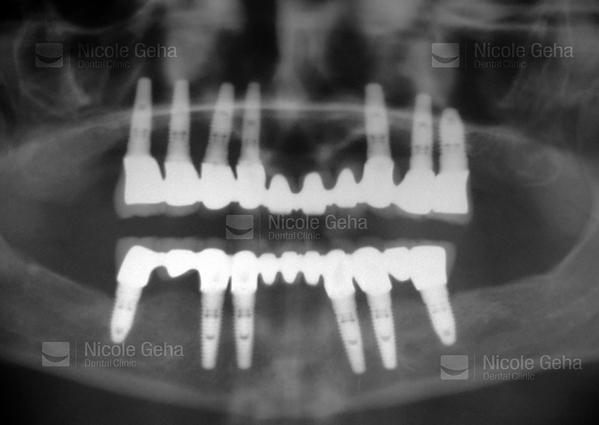

case 1: after